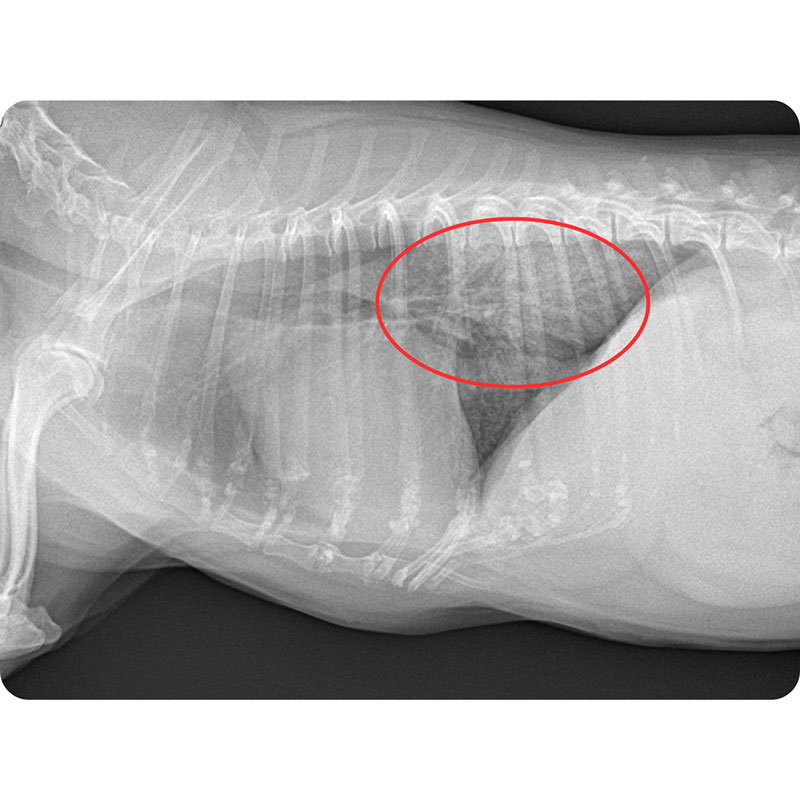

胸部X線検査

肺野に見られる浸潤影、気管支壁の肥厚、区域性の肺不透過像などを確認します。典型的な誤嚥性肺炎では、右中肺葉の異常がよく見られます。